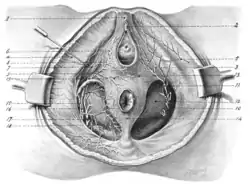

1, Suspensory ligaments of clitoris; 2, glans clitoridis; 3, posterior superficial perineal nerve; 4, fascia lata; 5, inferior pudendal nerve; 6, sphincter vaginac muscle; 7, erector clitoridis muscle; 8, superficial perineal artery; 9, transverse perineal artery; 10, obturator fascia; 1 1, anterior superficial perineal nerve; 12, anal fascia; 13, deep layer of superficial fascia; 14, external sphincter ani muscle; 15, dorsal nerve of clitoris; 16, internal pudic artery; 17, perineal | |

The dorsal nerve of the clitoris is a nerve in females that branches off the pudendal nerve[1] to innervate the clitoris. The nerve is important for female sexual pleasure,[2] and it may play a role in clitoral erections.[3]

It travels from below the inferior pubic ramus[4] to the suspensory ligament of the clitoris. At its thickest, the DNC is 2 mm (0.079 in) in diameter, visible to the naked eye during dissection.[2] The DNC splits into two nerve branches on either side of the midline, closely following the crura of the clitoris.[3]

The dorsal nerve of the clitoris is analogous to the dorsal nerve of the penis in males.[6] It is a terminal branch of the pudendal nerve.[1]